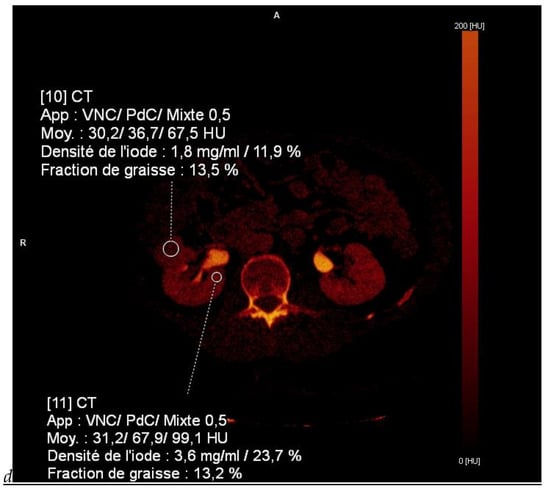

Figure 1.

Dual-energy CT aspect of a hypervascularized clear cell renal cell carcinoma of the upper pole of the right kidney. (a) Virtual unenhanced image. Note the presence of a solid exophytic renal mass in the upper pole of the right kidney. (b) The lesion enhances during the corticomedullary phase; measurement of the iodine concentration of the lesion (4.9 mg/mL) compared to that of the renal cortex (4.2 mg/mL) during the corticomedullary phase. (c) Monoenergetic image obtained at 40 keV during the nephrographic phase. Note the decrease in iodine concentration of the lesion (4.42 mg/mL) compared to that of the renal cortex (6.1 mg/mL). (d) Monoenergetic image obtained at 70 keV during the excretory phase. Compared to the monoenergetic image at 40 keV, the contrast between the lesion and the adjacent renal cortex is reduced. Note the washout of the lesion (iodine content: 1.8 mg/mL).